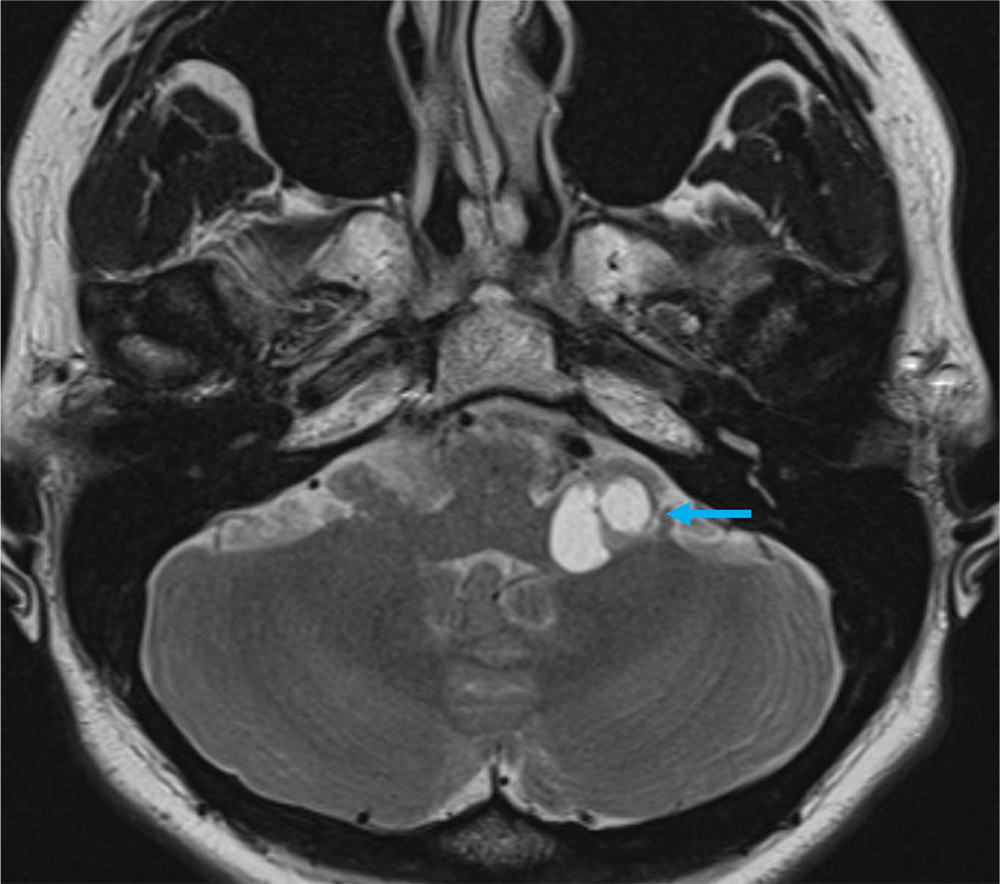

40歳代、女性、55kg、pilocytic astrocytoma

2か月前から頭重感および嘔気が持続しており、他院の単純CTにて左小脳腫瘍が疑われた。当院紹介となり、造影MRIが撮影された。

本症例では左小脳延髄角部に嚢胞成分を伴う腫瘍が存在し、左下位脳神経からの発生、もしくは小脳実質内腫瘍の鑑別が重要であった。前者であれば神経鞘腫、後者であればpilocytic astrocytomaの可能性が高くなる。3Dの脂肪抑制T1強調画像を撮影し、小脳実質内の可能性が高く、pilocytic astrocytomaを上位に考えた。手術が施行され、無事に完全摘出され上記の診断となった。

当該疾患の診断における造影MRIの役割

小脳腫瘍の鑑別において、造影MRIは必須である。本症例のように若年者の小脳実質内腫瘍の場合、特に血管芽腫との区別が重要となる。血管芽腫も嚢胞成分を伴う腫瘤を呈することが多いが、充実成分は強い造影効果を呈する。本症例は血管芽腫を疑うような強い造影効果とは言えず、pilocytic astrocytomaを疑うことが可能であった。